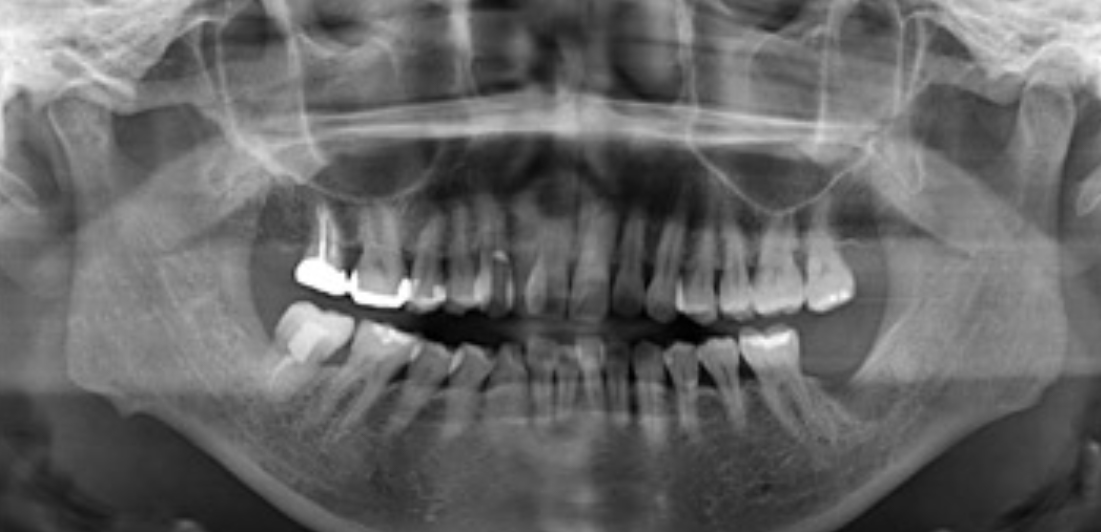

初診時のパノラマX線写真です。

初診時のパノラマX線写真です。左下の奥歯は支える骨が根尖までかなり吸収してしまっており、残念ながら抜歯になりました。

右下の奥歯に関してもパノラマX線写真ではそれほど骨吸収を起こしていなさそうでしたが、歯周ポケットを測ってみるとこちらも根尖の方まで吸収している事がわかりました。